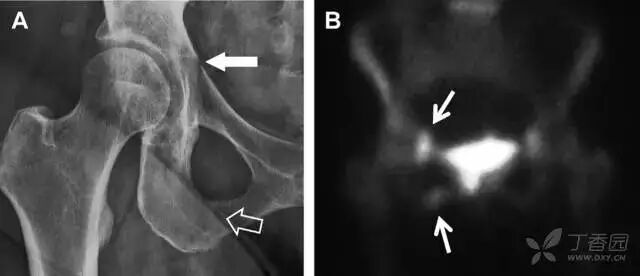

02耻骨骨折

具有持续损伤因素的耻骨支骨折,可能看似轻微,尤其是合并骨质疏松的患者。因此,特别需要注意皮质缺损和骨密度改变。长跑运动员易发生耻骨应力性骨折,常常发生在靠近耻骨联合的下支。由于这些骨折为非移位骨折,所以常常被忽视。

图 3 自行车事故患者,侧方受力的髋臼前柱/耻骨骨折。A 正位平片示右侧髂耻线轻微中断(实箭头),此处异常最初并未发现。此外,右下方其实还有一处轻微耻骨支骨折(空箭头)。B 10 天后行骨闪烁显像证实了髋臼前柱骨折和侧耻骨下支骨折(箭头)。值得注意的是,左侧前柱亦存在异常